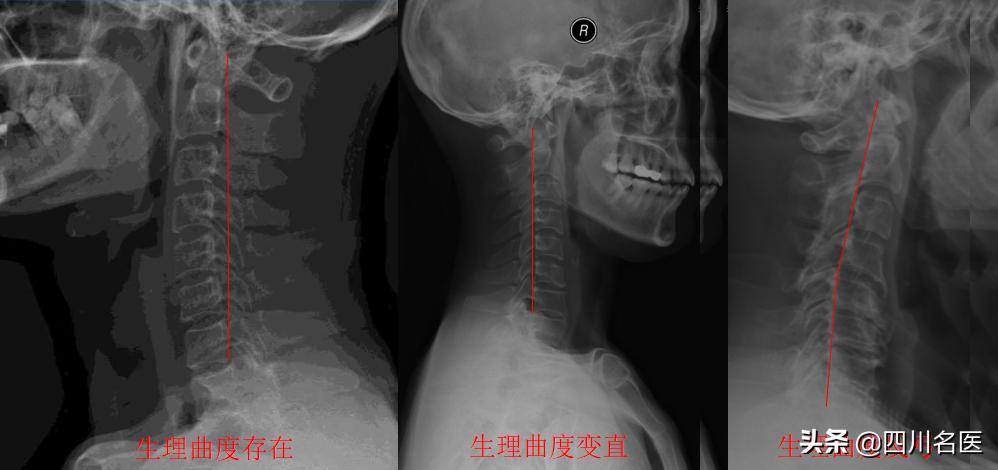

随后经过医生的检测,确诊为 由颈椎反弓引起的颈源性头痛 !换句话说就是,小华的颈椎弧度已经往反方向弯曲。